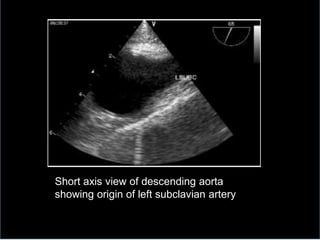

Short axis view of descending aorta

showing origin of left subclavian artery